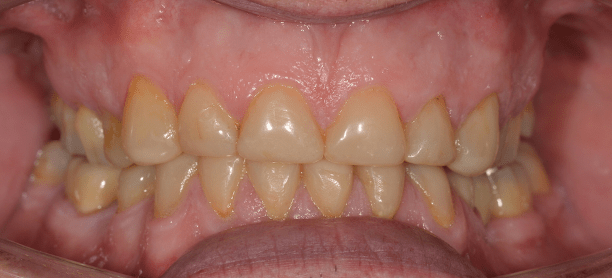

Direct composite is often used to treat toothwear. It is a minimally invasive method that does not damage the underlying tooth structure. It can chip, stain and fail. However, replacement and repair is more straightforward. This case was treated with direct composite alone.

Another case of mild toothwear and discolouration was treated with direct composite bonding.